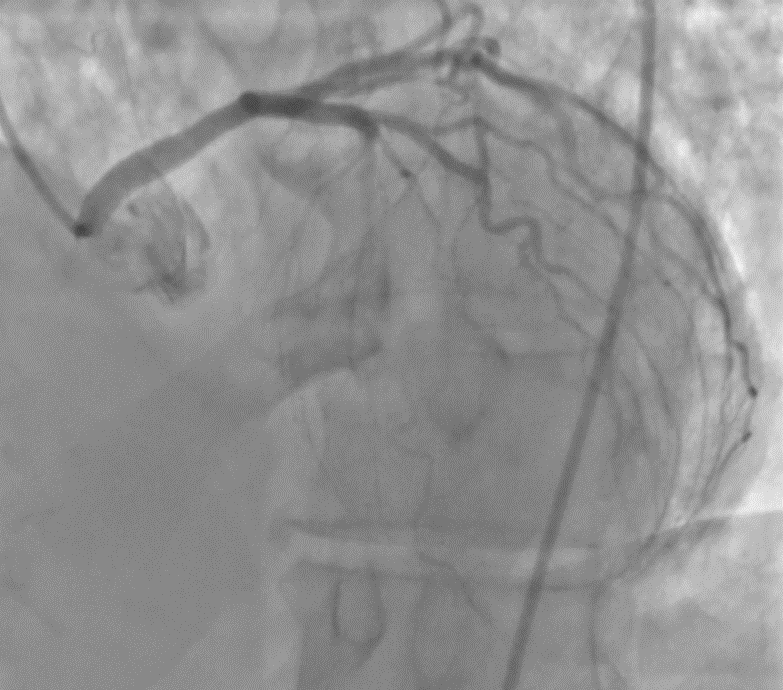

Background Congenital coronary artery anomalies have an estimated prevalence of approximately 1% in the general population. Some "malignant" variants, particularly the anomalous origin of the left coronary artery from the right sinus of Valsalva with an interarterial and/or intramural course, are associated with an increased risk of myocardial ischemia and sudden cardiac death. These anomalies are generally diagnosed at a young age, often during sports medicine screening. Case presentation A 63-year-old man was admitted to the cardiac intensive care unit after a witnessed out-of-hospital cardiac arrest occurring at rest, successfully treated in the pre-hospital setting for ventricular fibrillation with 2 defibrillation shocks and 1 mg of epinephrine. His medical history included treated arterial hypertension and known left bundle branch block (LBBB); occupation: butcher. On admission to the emergency department, electrocardiography showed sinus rhythm with LBBB, severe hypokalemia (K⁺ 2.6 mmol/L), and elevated troponin T (peak 205 ng/L). Transthoracic echocardiography (bad quality) revealed septal dyssynergy and mildly reduced left ventricular ejection fraction. Coronary angiography (CGF) showed no significant coronary stenoses and an ectopic origin of the left coronary artery from a non-coronary sinus, without clear definition of its course. Cardiac magnetic resonance imaging (MRI) was negative for fibrosis, necrosis, or myocarditis. During the diagnostic work-up, suspicious pelvic bone lesions were detected but subsequently ruled out as neoplastic by MRI and PET-CT. To complete the cardiological assessment, coronary computed tomography (CT) demonstrated origin of the left coronary artery from the right coronary sinus, with an acute take-off angle (<45°), a probable short intramural course, and an interarterial course between the aorta and pulmonary artery. Based on these findings, surgical correction with an unroofing procedure was indicated. Conclusions This case represents an atypical presentation of a "malignant" coronary anomaly given the age and mode of onset, occurring at rest in an adult patient. CGF and MRI may be insufficient in the anatomical characterization of coronary anomalies, while coronary CT remains the method of choice for defining the course and therapeutic strategy. Clinical suspicion remains a fundamental element in identifying causes of cardiac arrest that are only apparently idiopathic.